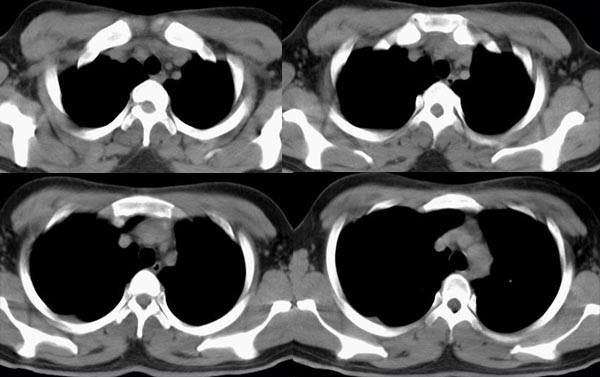

m21y既往体健,否认结核、支扩等病史;1周前患上感,无明显咳嗽,自觉无明显不适。单位体检透视时发现右侧液气胸!cr及ct如下(肺组织窗:l:-598hu w:1132hu):请大家会诊!!

右侧巨大含气囊性病变,壁薄、光整、其外侧见气体。右肺压迫性肺不张、胸腔内见少量积液。纵隔向左侧移位。左肺未见异常。诊断:1.右侧含气肺囊肿(先天性)。2.右侧液气胸。(少量液体)3.右肺压迫性肺不张。我也遇见一例这样的病人。女性。股骨外伤就诊。常规胸片发现右侧囊性病变。